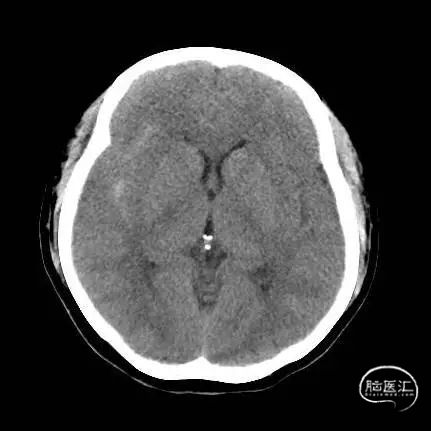

术前头部CT:

根据造影结合患者头部CT出血分布考虑朝上方的较大动脉瘤(1.3mm*1.2mm)为破裂出血的责任动脉瘤,但是其瘤体小难以致密填塞,并且朝下的微小动脉瘤约0.8mm,难以进行弹簧圈填塞,故考虑破裂动脉瘤予以1枚弹簧圈疏松填塞加快瘤内血栓形成后置入密网支架覆盖上下两枚动脉瘤进行血管壁修复。

根据造影结合患者头部CT出血分布考虑朝上方的较大动脉瘤(1.3mm*1.2mm)为破裂出血的责任动脉瘤,但是其瘤体小难以致密填塞,并且朝下的微小动脉瘤约0.8mm,难以进行弹簧圈填塞,故考虑破裂动脉瘤予以1枚弹簧圈疏松填塞加快瘤内血栓形成后置入密网支架覆盖上下两枚动脉瘤进行血管壁修复。